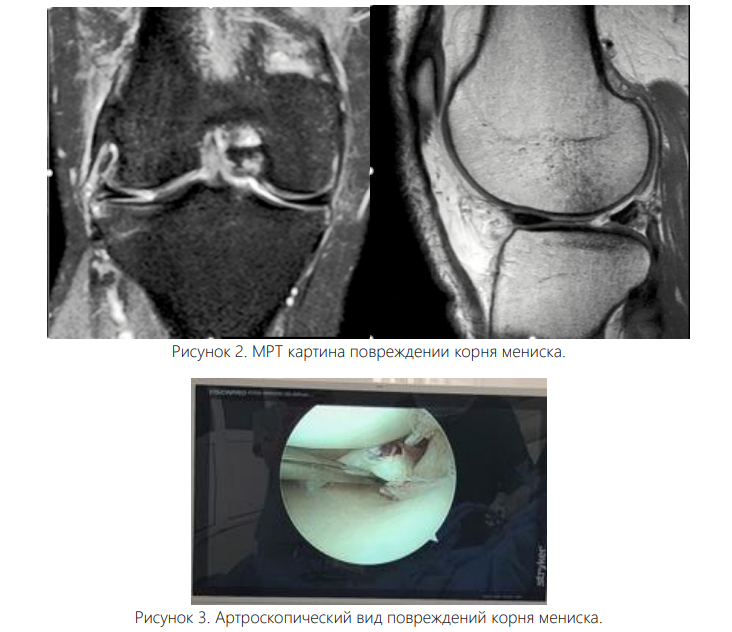

МРТ по-прежнему является золотым стандартом для выявления РКМ с помощью визуализации, причем предпочтительным методом являются Т-2-взвешенные изображения [7, 15].

Несколько классических находок могут помочь выявить наличие патологии корня мениска. К ним относятся «признак усечения» (наличие вертикального линейного дефекта у корня мениска на коронарных сериях, часто с выпячиванием мениска), «признак призрака» (отсутствие нормального сигнала мениска на сагиттальных сериях) и «радиальный разрыв» (высокий сигнал, линейные интенсивности, появляющиеся перпендикулярно корню мениска на аксиальных сериях) [15]. Рисунок 2. МРТ картина повреждении корня мениска.

Несмотря на эти признаки, было отмечено, что МРТ может не обнаружить разрывы. Бхатиа и соавторы сообщили, что до 1/3 медиальных РКМ могут быть пропущены при визуализации [7].

Аналогичным образом, Krych и коллеги дополнительно продемонстрировали, что предоперационная МРТ, прочитанная радиологами, прошедшими обучение в области опорно-двигательного аппарата, обнаружила только 33% латеральных РКМ, и только 50% известных разрывов были «явно заметны» на изображениях, повторно проанализированных после операции [12]. Таким образом, хотя МРТ остается наиболее надежным нехирургическим методом выявления РКМ, хирурги должны осознавать возможность пропущенных диагнозов и тщательно исследовать задний корень латерального мениска во время артроскопии. Классификация. Классификация травм на основе морфологии разрыва позволяет улучшить диагностику и лечение. Система классификации, описанная LaPrade et al. [11], остается действующим стандартом. Тип 1 (7 %) — частичный, механически стабильный разрыв. Тип 2 (68%) — полные радиальные разрывы, происходящие в пределах 9 мм от костного прикрепления корня. Тип 3 (6%) — полное отслоение корня с сопутствующим разрывом в виде ручки ведра. Тип 4 (10%) — полное отслоение корня на фоне сложных косых разрывов. Тип 5 (9%) — костные отрывные переломы в месте прикрепления корня [15, 16].